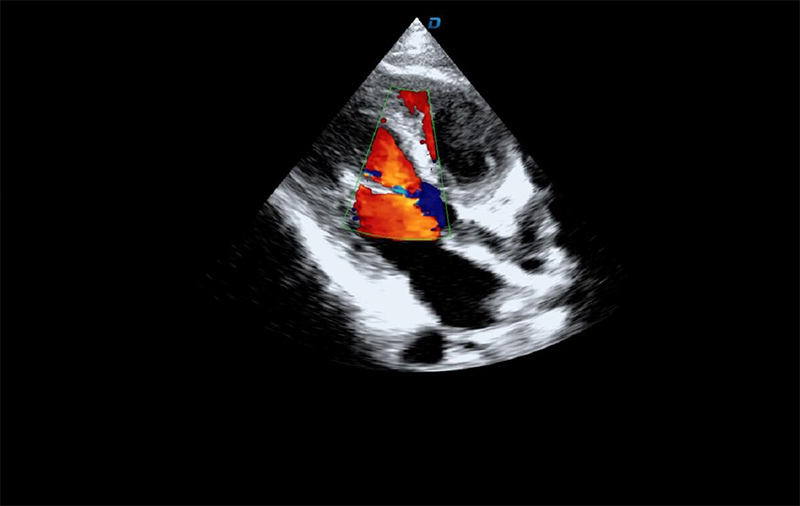

心臟彩超機檢查

有些心臟病會引起心臟電活動的改變,但是有些心臟的疾病卻不影響心電,而只影響心臟本身的結構。比如心臟擴大,心臟收縮無力,心臟的瓣膜關閉不嚴密,這些疾病的診斷及發現更多的依賴于心臟彩超,這些病變一般不隨癥狀的緩解而緩解。心臟超聲心動圖,不需要開胸,就可以看到心臟的大小、內部結構、瓣膜運動情況等。除了探頭壓迫可能會有疼痛或不適感外,對患者沒有任何創傷。

臨床上,心臟超聲心動圖主要用于對各種先心病、心臟瓣膜病的診斷;各種心肌病、心包疾病的診斷和心臟功能的評估。部分嚴重肺氣腫、胸廓畸形等患者,因為超聲圖像質量欠佳而診斷效果受到一定限制。

大為T8心臟彩超機

心臟彩超機檢測圖